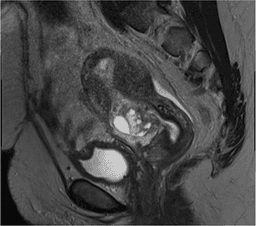

- A cesarean scar ectopic pregnancy occurs when the pregnancy implants along the scar tissue deep in the myometrium from a prior cesarean surgery, felt to be precipitated by a small fissure or fistula residual in the scar

- Diagnosis can be challenging and ultrasound may not clearly show this type of ectopic pregnancy

- MRI has been successfully used for diagnosis as well